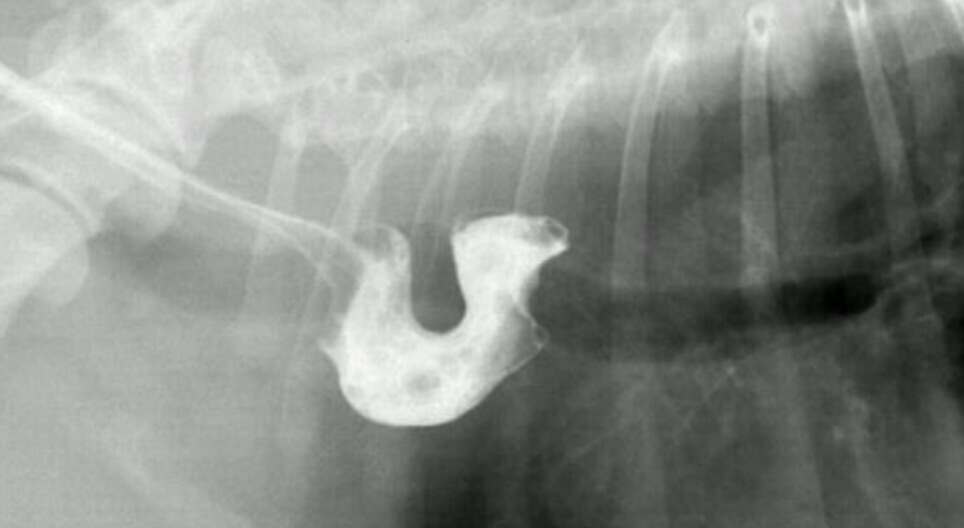

| Esophageal diverticulum (์๋๊ฒ์ค) |

| - ์๋๋ฒฝ์ด ์ฃผ๋จธ๋์ฒ๋ผ ๋์ถ๋จ. - ๊ฒ์ค ๋ด์ ์กฐ์์ ๊ฐ ๊ณ ์. |

![]() ![]() |